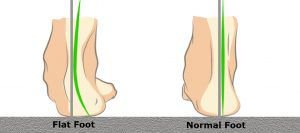

Per piede piatto, di fatto si intende un abbassamento della volta plantare di entità variabile sino al suo completo appiattimento, spesso associato a valgismo del retro piede (calcagno).

Questo atteggiamento (pronazione) può essere di gravità variabile e comportare diverse problematiche.

Nei bambini con il piede piatto, l’arco plantare scompare quando si è in piedi.